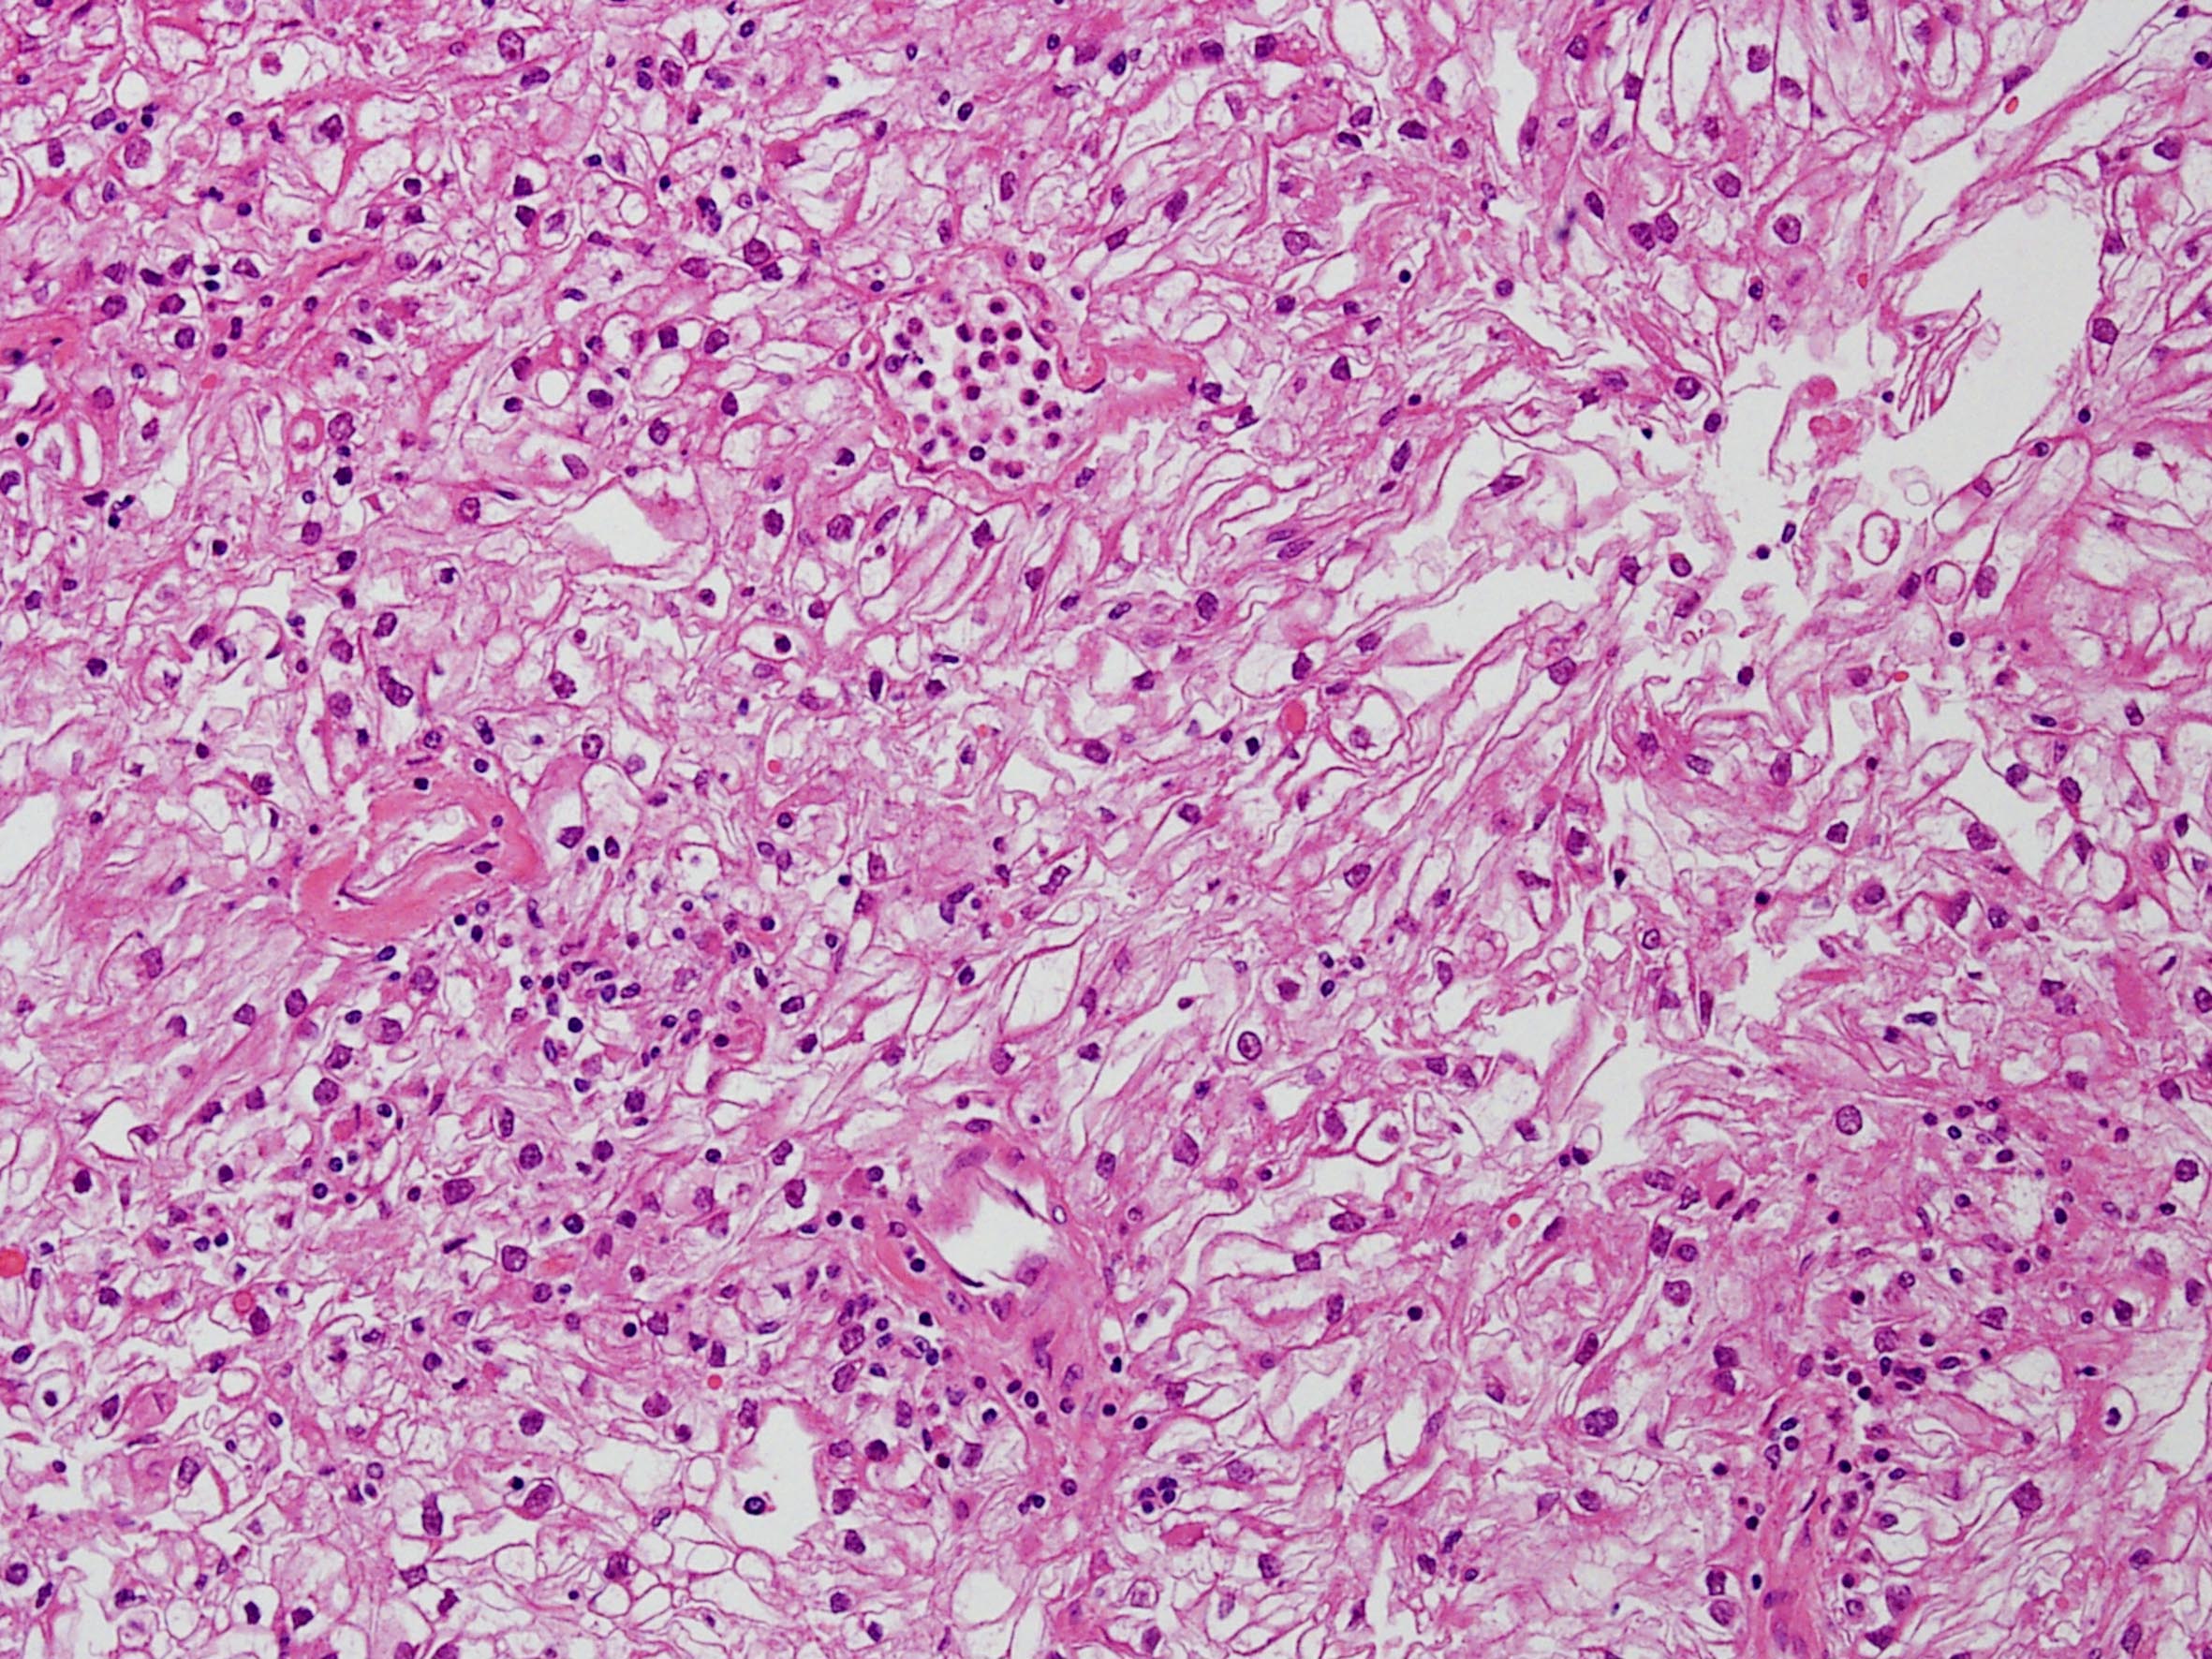

Classification of renal tumors

Case ID: 258